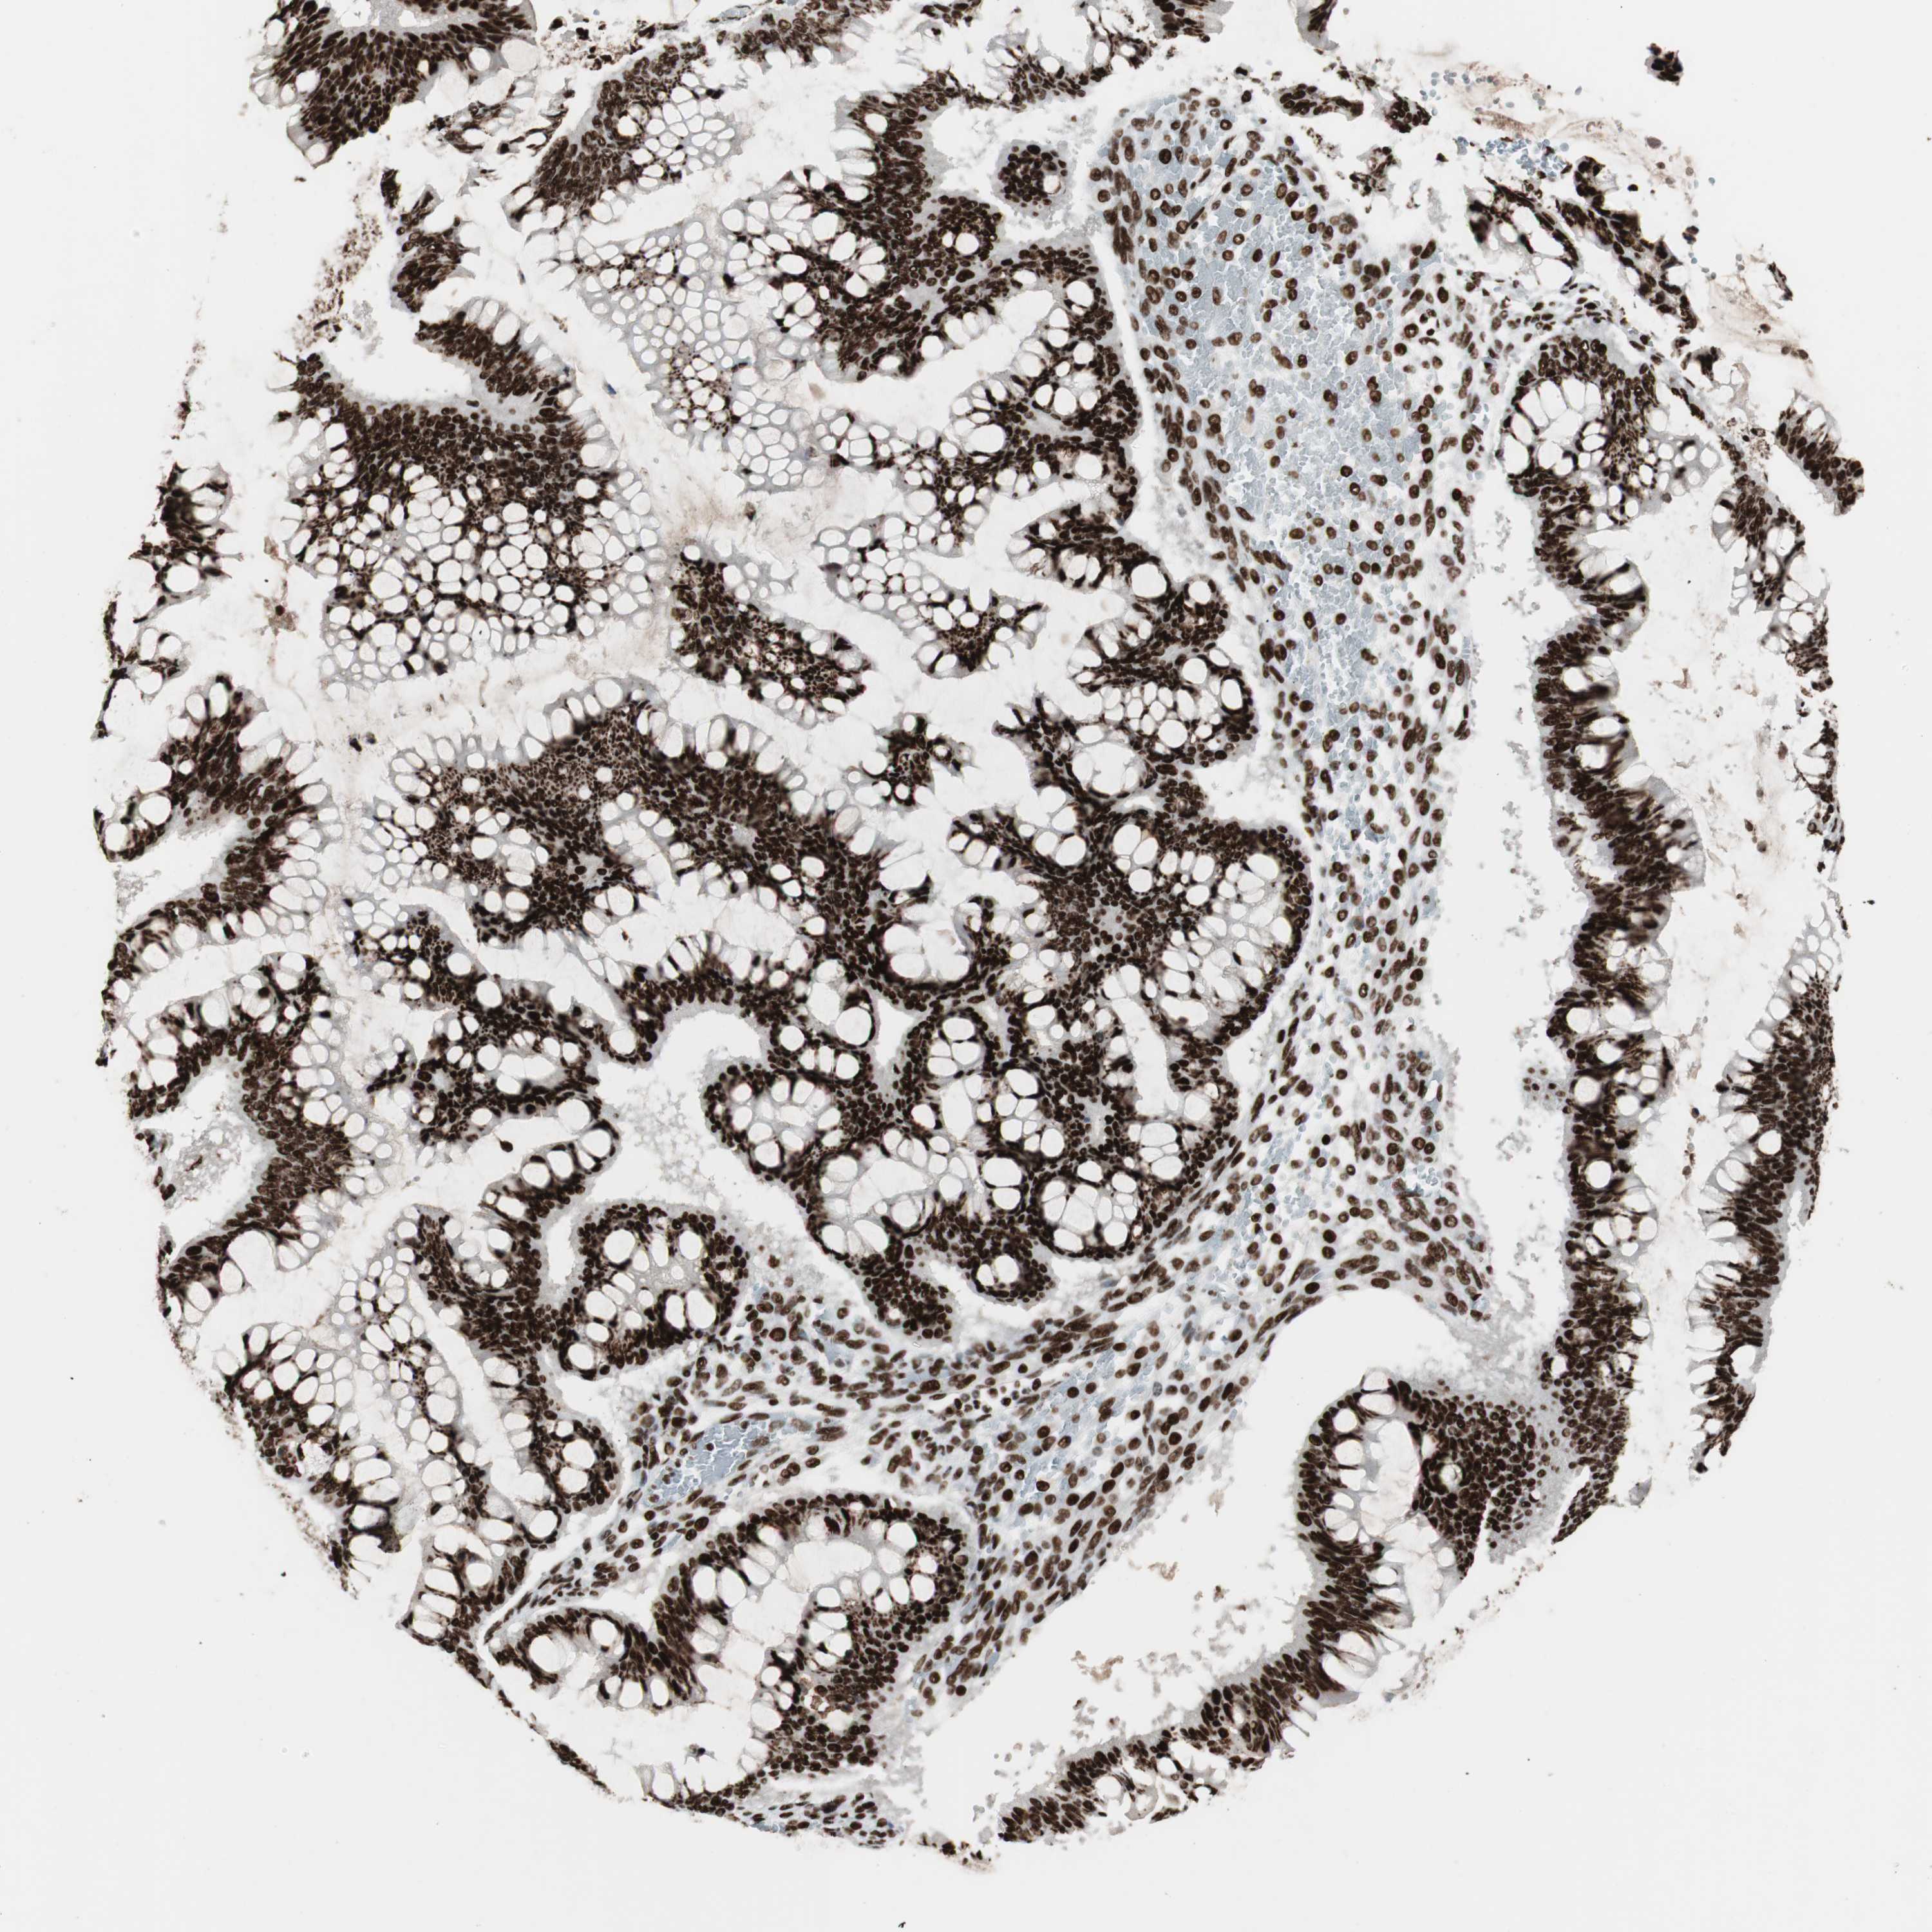

OVARIAN CANCER - Protein expressioni

A mouse-over function shows sample information and annotation data. Click on an image to view it in a full screen mode. Samples can be filtered based on level of antibody staining by selecting one or several of the following categories: high, medium, low and not detected. The assay and annotation is described here.

Note that samples used for immunohistochemistry by the Human Protein Atlas do not correspond to samples in the TCGA dataset.

Antibody stainingi

Antibody staining in the annotated cell types in the current human tissue is reported as not detected, low, medium, or high, based on conventional immunohistochemistry profiling in selected tissues. This score is based on the combination of the staining intensity and fraction of stained cells.

Each image is clickable and will lead to virtual microscopy that enables deeper exploration of all samples and also displays staining intensity scores, fraction scores and subcellular localization as well as patient and tissue information for each sample.

Antibody HPA012510

Antibody CAB008388

Staining

High

Medium

Low

Not detected

Intensity

Strong

Moderate

Weak

Negative

Quantity

>75%

75%-25%

<25%

None

Location

Nuclear

Cytoplasmic/membranous

Cytoplasmic/membranous,nuclear

Cystadenocarcinoma, serous, NOS

Carcinoma, endometroid

Cystadenocarcinoma, mucinous, NOS

Carcinoma, NOS